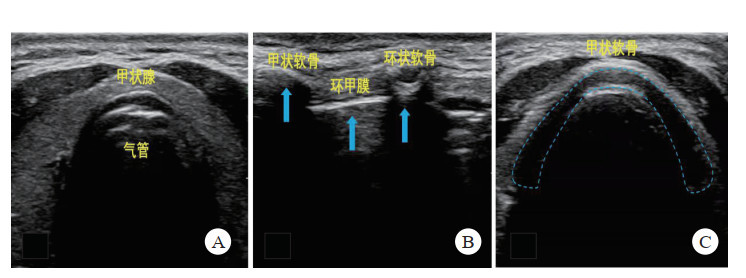

2.2 气道紧急气道管理(emergency airway management, EAM)是急危重症时保持气道通畅的重要手段。在空间站任务特殊环境中,一旦出现伤情,往往伤情重、时间紧、当手法开放气道、口/鼻通气管、喉罩等方法无效,需行气管插管以获得确定性人工气道时,因受伤情或航天服制约,可能导首次气管插管尝试成功率低。如果航天员遭受严重的颅脑、颈椎或胸部外伤等需要进行紧急开通气道,如不能顺利完成气管插管,需要行紧急的环甲膜穿刺切开。虽然触诊仍是识别环甲膜的传统方法,但大量研究表明,即使在最理想的条件下,也不完全可靠,尤其在紧急情况或解剖结构变异时,其可靠性显著降低[29]。超声可协助临床医生快速筛查不易行喉镜检查的困难气道,既往研究表明在急救过程中经超声环甲膜定位的时间,最短(17±9.2)s[30],最长(196.1±60.6)s[31]。有研究对多名无超声经验的非麻醉专业的临床医生进行超声引导下环甲膜穿刺定位培训后,定位成功率达88.3%,用时(36.9±9.0) s[32]。在超声引导下行环甲膜定位穿刺切开术简单易行,准确性高,用时短,不延误总体抢救时间,且便携超声可携带至舱前,在紧急情况下,实用性极强。

检查方法:采用高频(5.0~10.0 MHz)线阵探头,将探头放置颈部环状软骨以下,取横向切面,由下而上纵向平扫,快速扫描确定环甲膜位置(图 4)。此操作一般控制在2 min内。

|

| 图A-C为由环状软骨以下定位纵行向上滑动至甲状软骨; A:环状软骨以下气管处; B:甲状软骨与环状软骨交界处;C:图甲状软骨处 图 4 超声引导下横向切面环甲膜穿刺定位示意图 |

|

|

【推荐意见3】航天员在紧急抢救时,如因各种原因无法通畅气道,可在便携超声引导下行紧急环甲膜穿刺术。